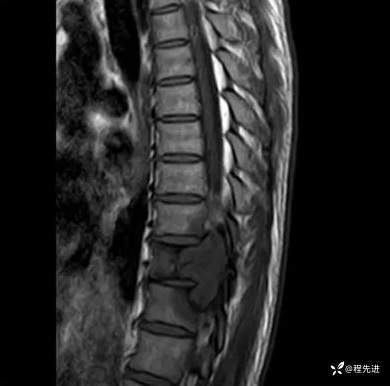

MR:

T1: